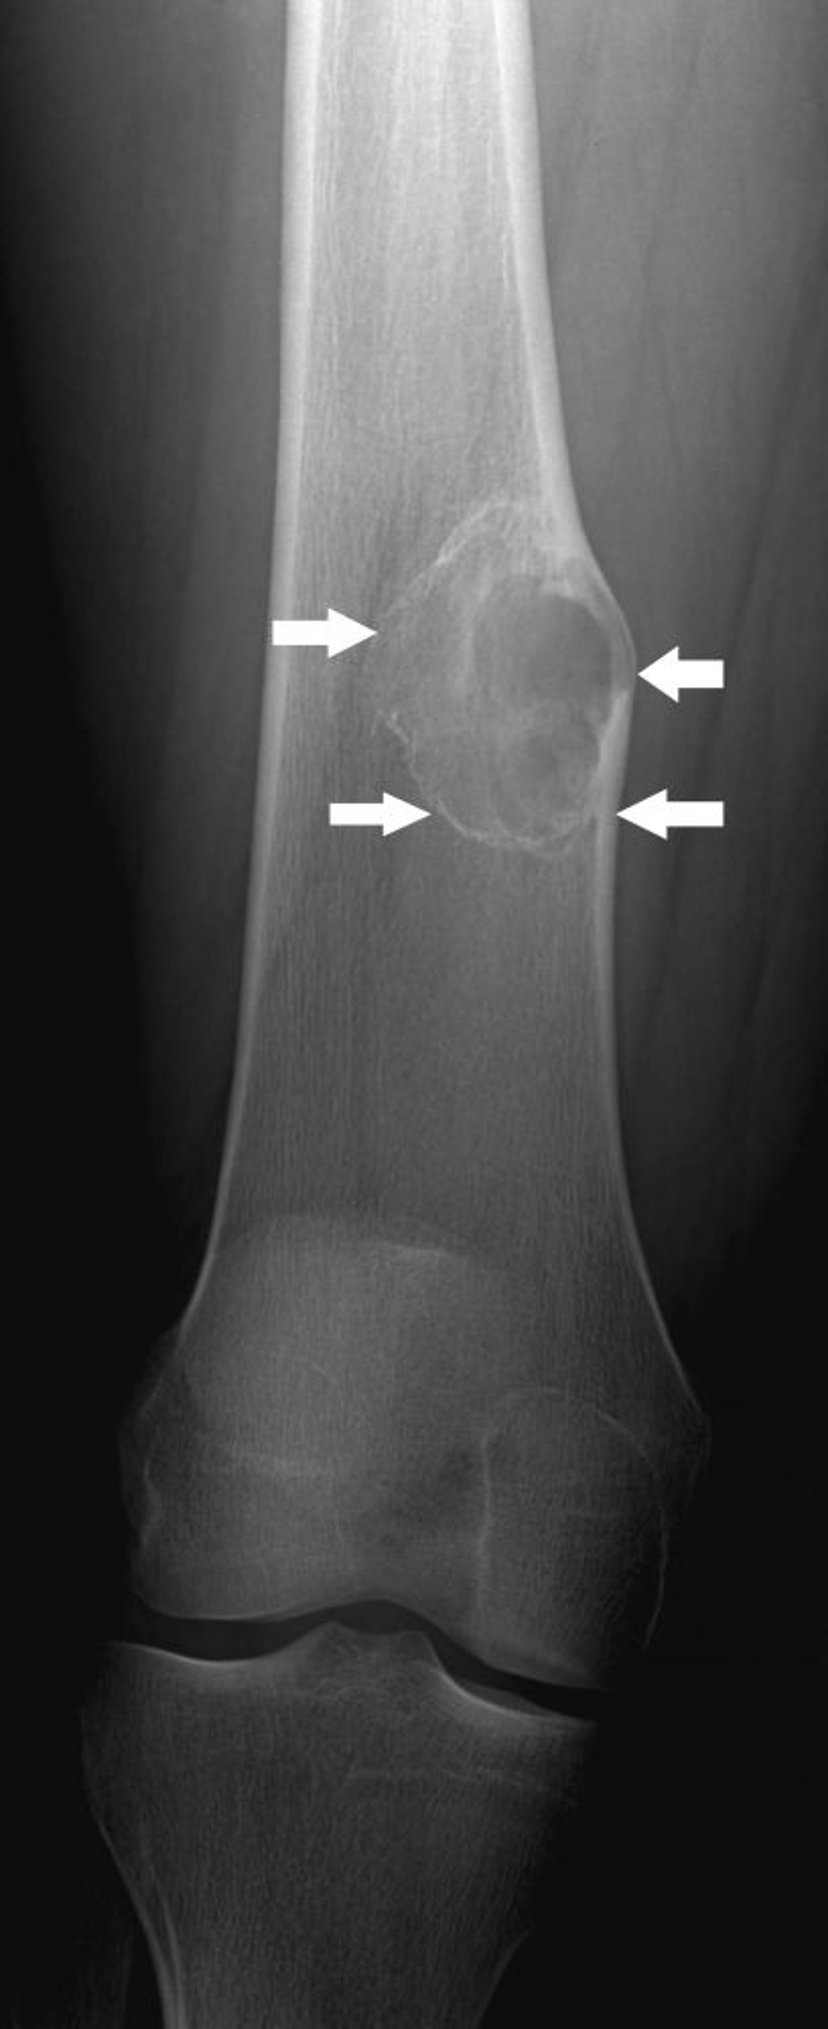

이 무릎 X-레이는 무릎 관절 위 허벅지뼈 표면의 성장물(화살표)인 뼈연골종을 보여줍니다.

이미지 제공: Michael J. Joyce, MD 및 Hakan Ilaslan, MD.